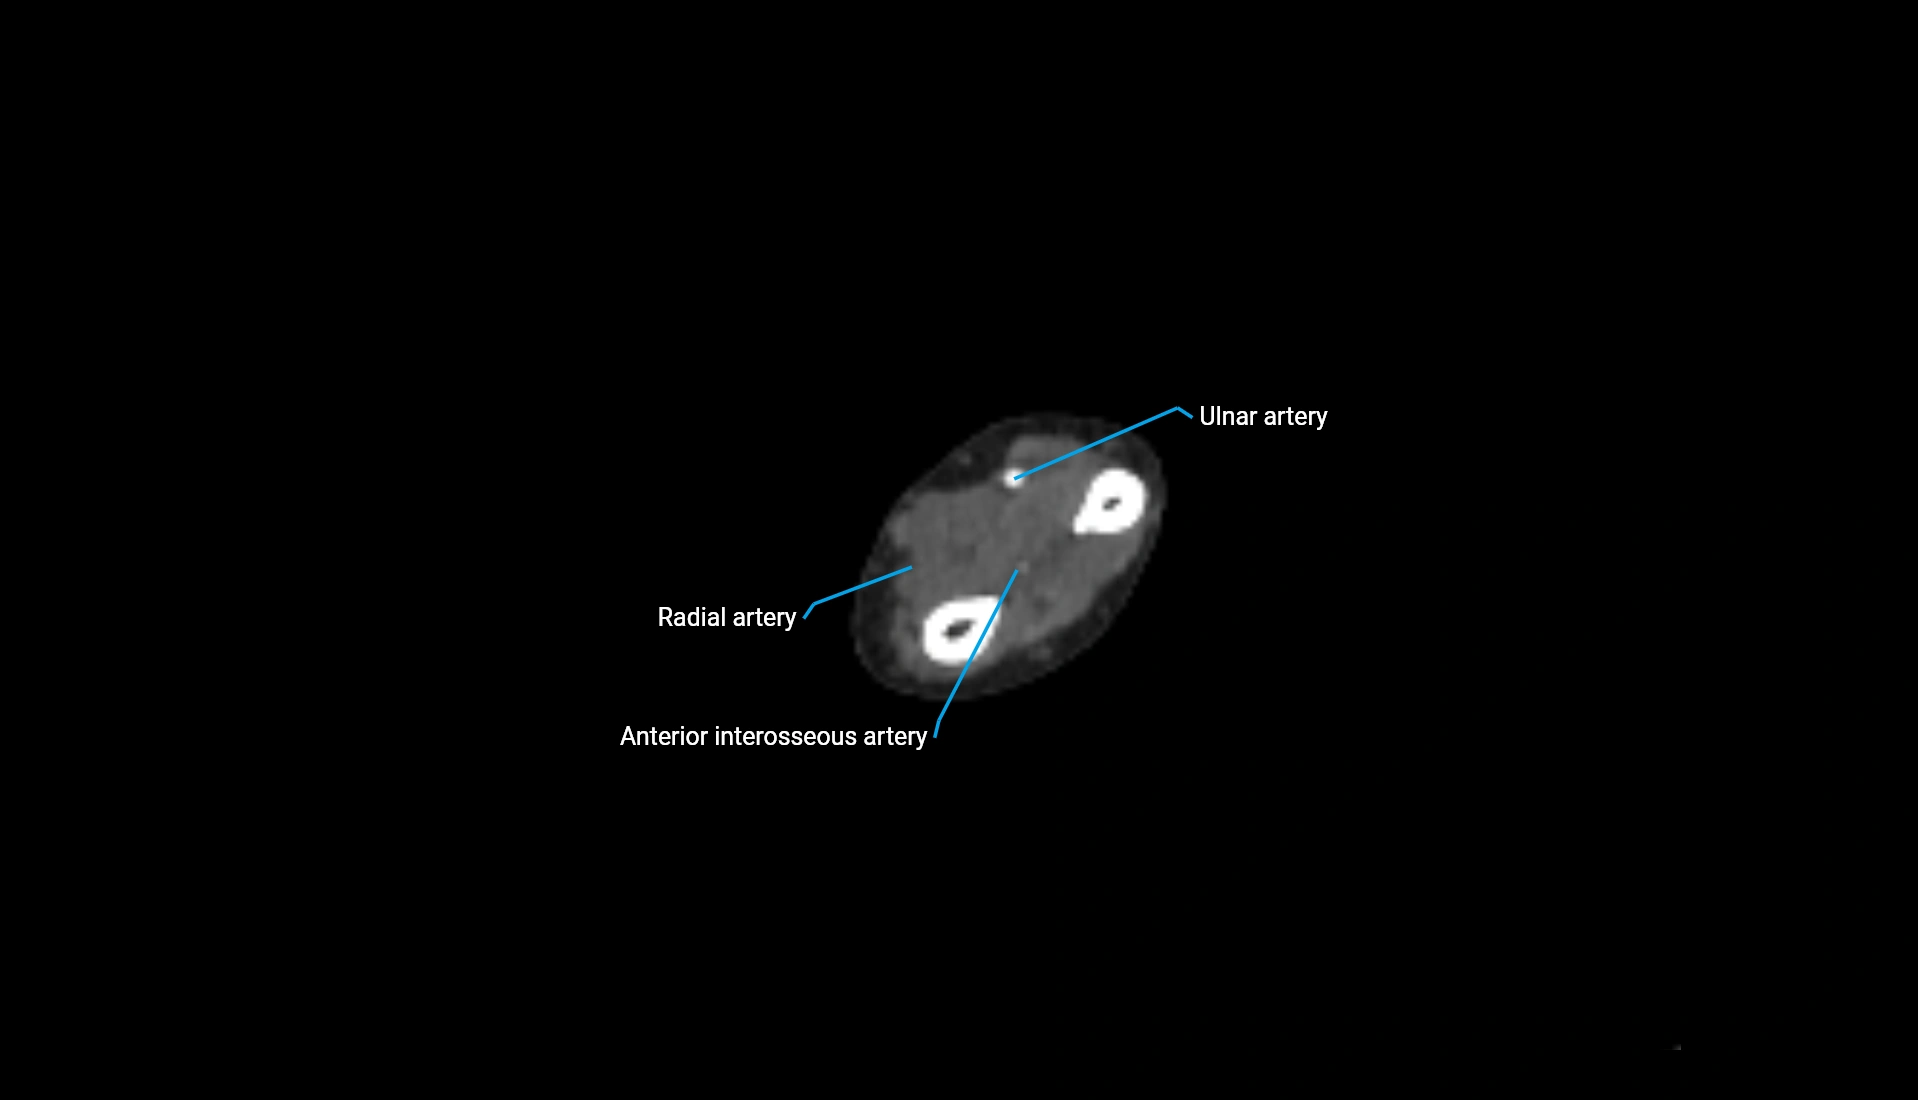

CT Appearance

Non-Contrast CT:

• Cortex: High-density, sharply defined

• Subchondral bone: Dense cancellous matrix

• Articular surface: Smooth concave contour articulating with the capitellum

• Excellent for evaluating bone integrity, alignment, and subtle fractures

Post-Contrast CT:

• Bone: No enhancement

• Joint capsule and synovium: Mild enhancement outlining the joint

• Improves contrast between soft tissues and bony margins

• Useful in detecting subtle joint abnormalities or postoperative changes